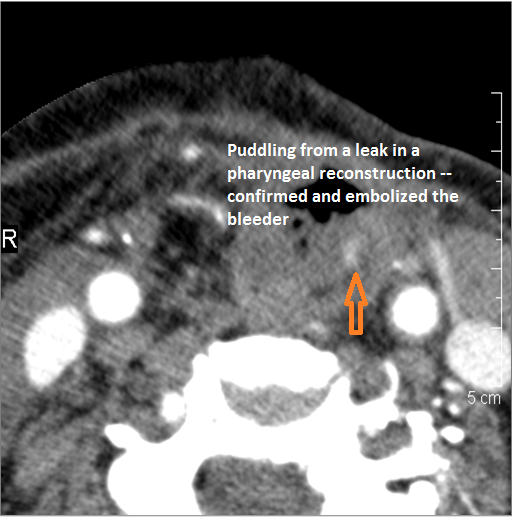

Vascular Findings

There is evidence of active extravasation or a contained leakage from an arterial source. [Yes/No]